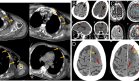

El tórax mostraba pectus excavatum con asimetría mamaria correspondiente a Tanner II. Los genitales externos eran femeninos normales, también en estadio Tanner II. La columna vertebral no presentaba alteraciones evidentes, mientras que en las extremidades se palpaban tumoraciones en el tercio externo de la clavícula izquierda, húmero proximal izquierdo y una deformidad en la tibia proximal anterior izquierda.

Las imágenes radiológicas demostraron exóstosis en astrágalo derecho, lesión en espina tibial anterior izquierda y nuevas lesiones en clavícula izquierda. El estudio histopatológico confirmó el diagnóstico de osteocondroma benigno en todas las lesiones resecadas.